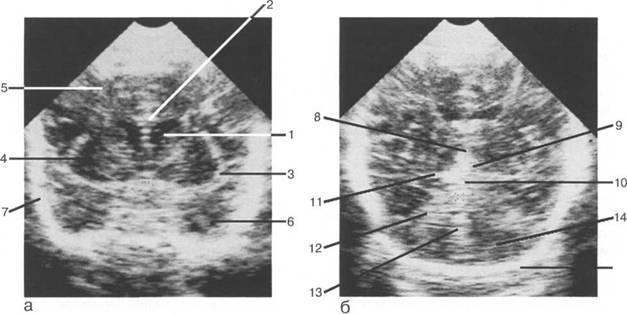

гиперэхогенными - выглядят кости череп 13513u2010n 72;. Сосудистые сплетения желудочков также гипер-эхогенны. Особенно хорошо лоцируются сплетения боковых желудочков, которые, распрост

рога боковых желудочков; б - через структуры задней череп 13513u2010n 85;ой ямки.

IV IV IV IV III IV